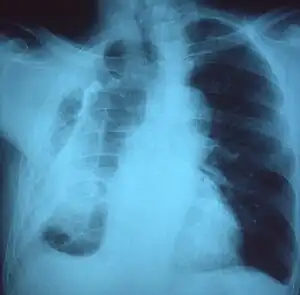

A fibrothorax can typically be diagnosed by taking an appropriate medical history in combination with the use of appropriate imaging techniques such as a plain chest X-ray or CT scan.[1] These imaging techniques can detect fibrothorax and pleural thickening that surround the lungs.[11] The presence of a thickened peel with or without calcification are common features of fibrothorax when imaged.[1] CT scans can more readily differentiate whether pleural thickening is due to extra fat deposition or true pleural thickening than X-rays.[1]

If a fibrothorax is severe, the thickening may restrict the lung on the affected side causing a loss of lung volume.[11] Additionally, the mediastinum may be physically shifted toward the affected side.[1] A reduction in the size of one side of the chest (hemithorax) on an X-ray or CT scan of the chest suggests chronic scarring.[9] Signs of the underlying disease causing the fibrothorax are also occasionally seen on the X-ray.[9] A CT scan may show features similar to those seen on a plain X-ray.[11] Lung function testing typically demonstrates findings consistent with restrictive lung disease.[9]

CXR of an individual affected by fibrothorax (consequence of tuberculosis) -

Extensive left-sided fibrothorax -

Chest radiograph displaying inhomogeneous opacification of the left half of the chest that is fibrothorax -